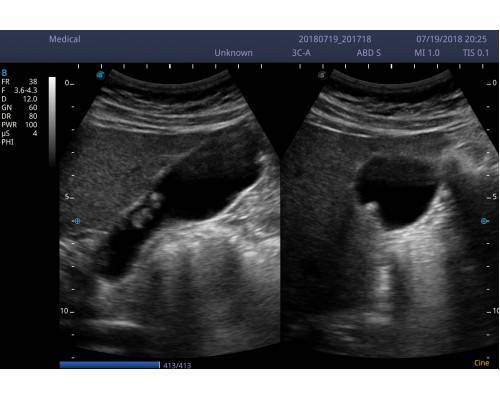

και μοντέρνας εμφάνισης του. Εξυπηρετεί τις ανάγκες όλων σχεδόν των ειδικοτήτων

• Εικόνα 2 διαστάσεων 2D (B mode),2B(δίπλες εικόνες), 4B(τετραπλές εικόνες), M mode, PW (pulse wave Doppler,CFM (color),PDI(power)DirPDI (κατεύθυνση ροής )CW .

• THI(αρμόνικες συχνότητες )

• Pulse inversion harmonic imaging(δημιουργεί αντίθεση μεταξύ των ιστών έχοντας κατά συνέπεια πολύ καλύτερη ποιότητα εικόνας.

• Spatial compound imaging(σάρωση από διαφορετικές οπτικές γωνίες σε πραγματικό χρόνο πολύ καλύτερη απεικόνιση)

• M-scan (speckle reduction technology, αλγόριθμος που αυξάνει την ποιότητα της εικόνας κατά πολύ.)

3C-A (ABD-OB-GYN) 1.O-7.0MHZ 50mm